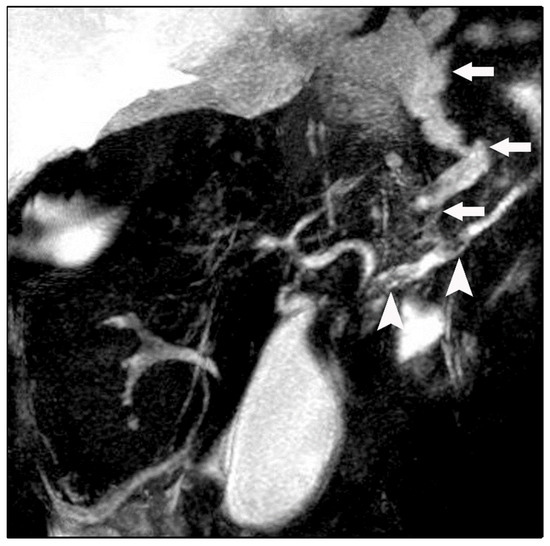

Bilateral Pancreaticopleural Fistula Masquerading as Thoracic Disease in Chronic Calculous Pancreatitis

Background: Pancreaticopleural fistula is a rare complication of chronic pancreatitis resulting from pancreatic duct disruption, typically presenting with pleural effusion and predominant respiratory symptoms. Bilateral pleural involvement is exceptionally uncommon and poses significant diagnostic and therapeutic challenges. Case Presentation: A 56-year-old [...] Read more.

Background: Pancreaticopleural fistula is a rare complication of chronic pancreatitis resulting from pancreatic duct disruption, typically presenting with pleural effusion and predominant respiratory symptoms. Bilateral pleural involvement is exceptionally uncommon and poses significant diagnostic and therapeutic challenges. Case Presentation: A 56-year-old man with a history of chronic alcohol abuse presented with progressive dyspnea and mild epigastric pain. Imaging revealed bilateral pleural effusions, an atrophic pancreas with a markedly dilated main pancreatic duct containing calculi, and a fistulous tract extending from the pancreatic body through the esophageal hiatus into the mediastinum. Magnetic resonance cholangiopancreatography confirmed the diagnosis of chronic calculous pancreatitis complicated by a pancreaticopleural fistula. After unsuccessful conservative management, the patient underwent distal pancreatectomy, resection of the fistulous tract, and Roux-en-Y pancreatojejunostomy. The postoperative course was uneventful, with complete resolution of pleural effusions and sustained clinical improvement. Conclusions: This case highlights the importance of considering pancreaticopleural fistula in patients with unexplained pleural effusions and minimal abdominal symptoms, particularly in the context of chronic pancreatitis. Bilateral involvement, although rare, should not preclude timely diagnosis. Appropriate diagnostic studies by computed tomography, magnetic resonance imaging, and magnetic resonance cholangiopancreatography are crucial for establishing the diagnosis. Surgical management offers definitive treatment in patients with ductal obstruction and calculous disease, resulting in excellent long- term outcomes. Full article